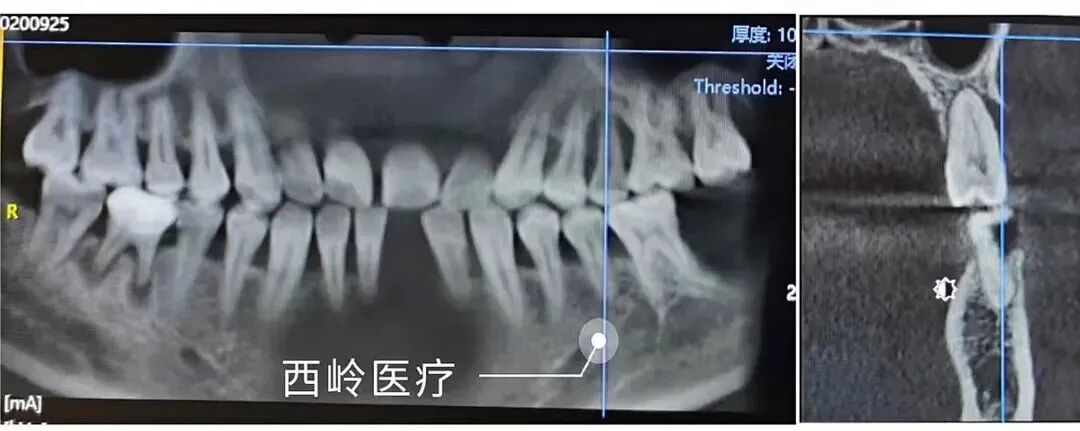

2020-9-25初診

CBCT顯示:#25唇側牙槽骨吸收達根尖。#26腭側根牙槽骨吸收達根尖,與上頜竇僅薄層骨壁相隔。#27唇側牙槽骨吸收達根尖.